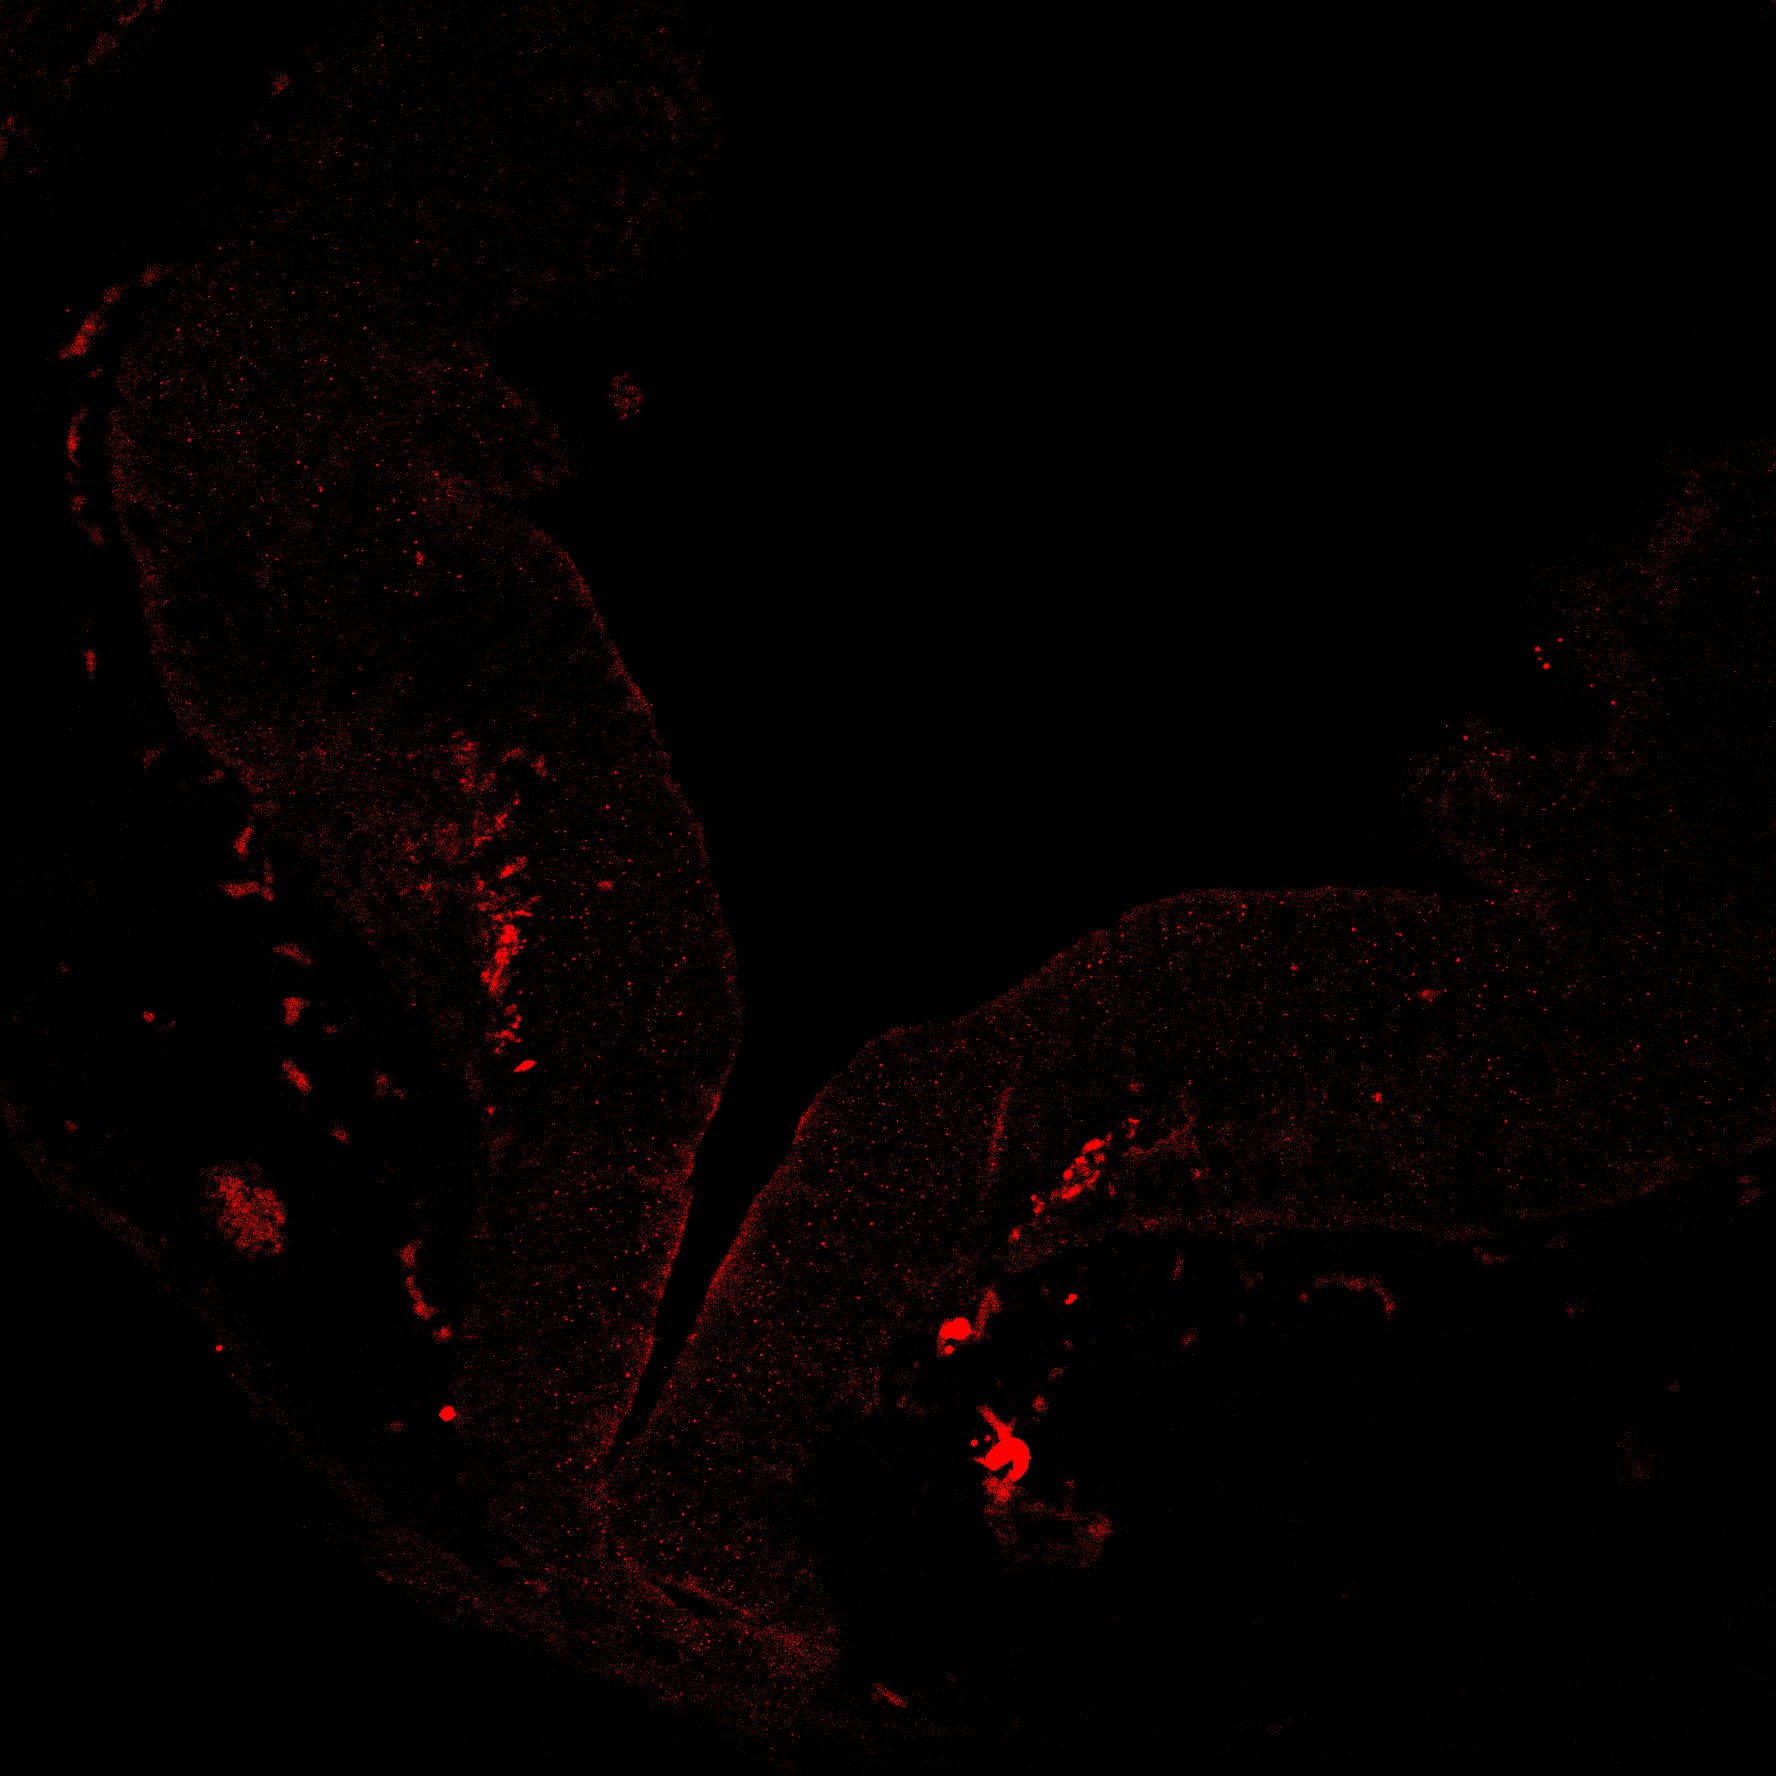

TH

6PCW human midbrain

7PCW human midbrain

11PCW human midbrain